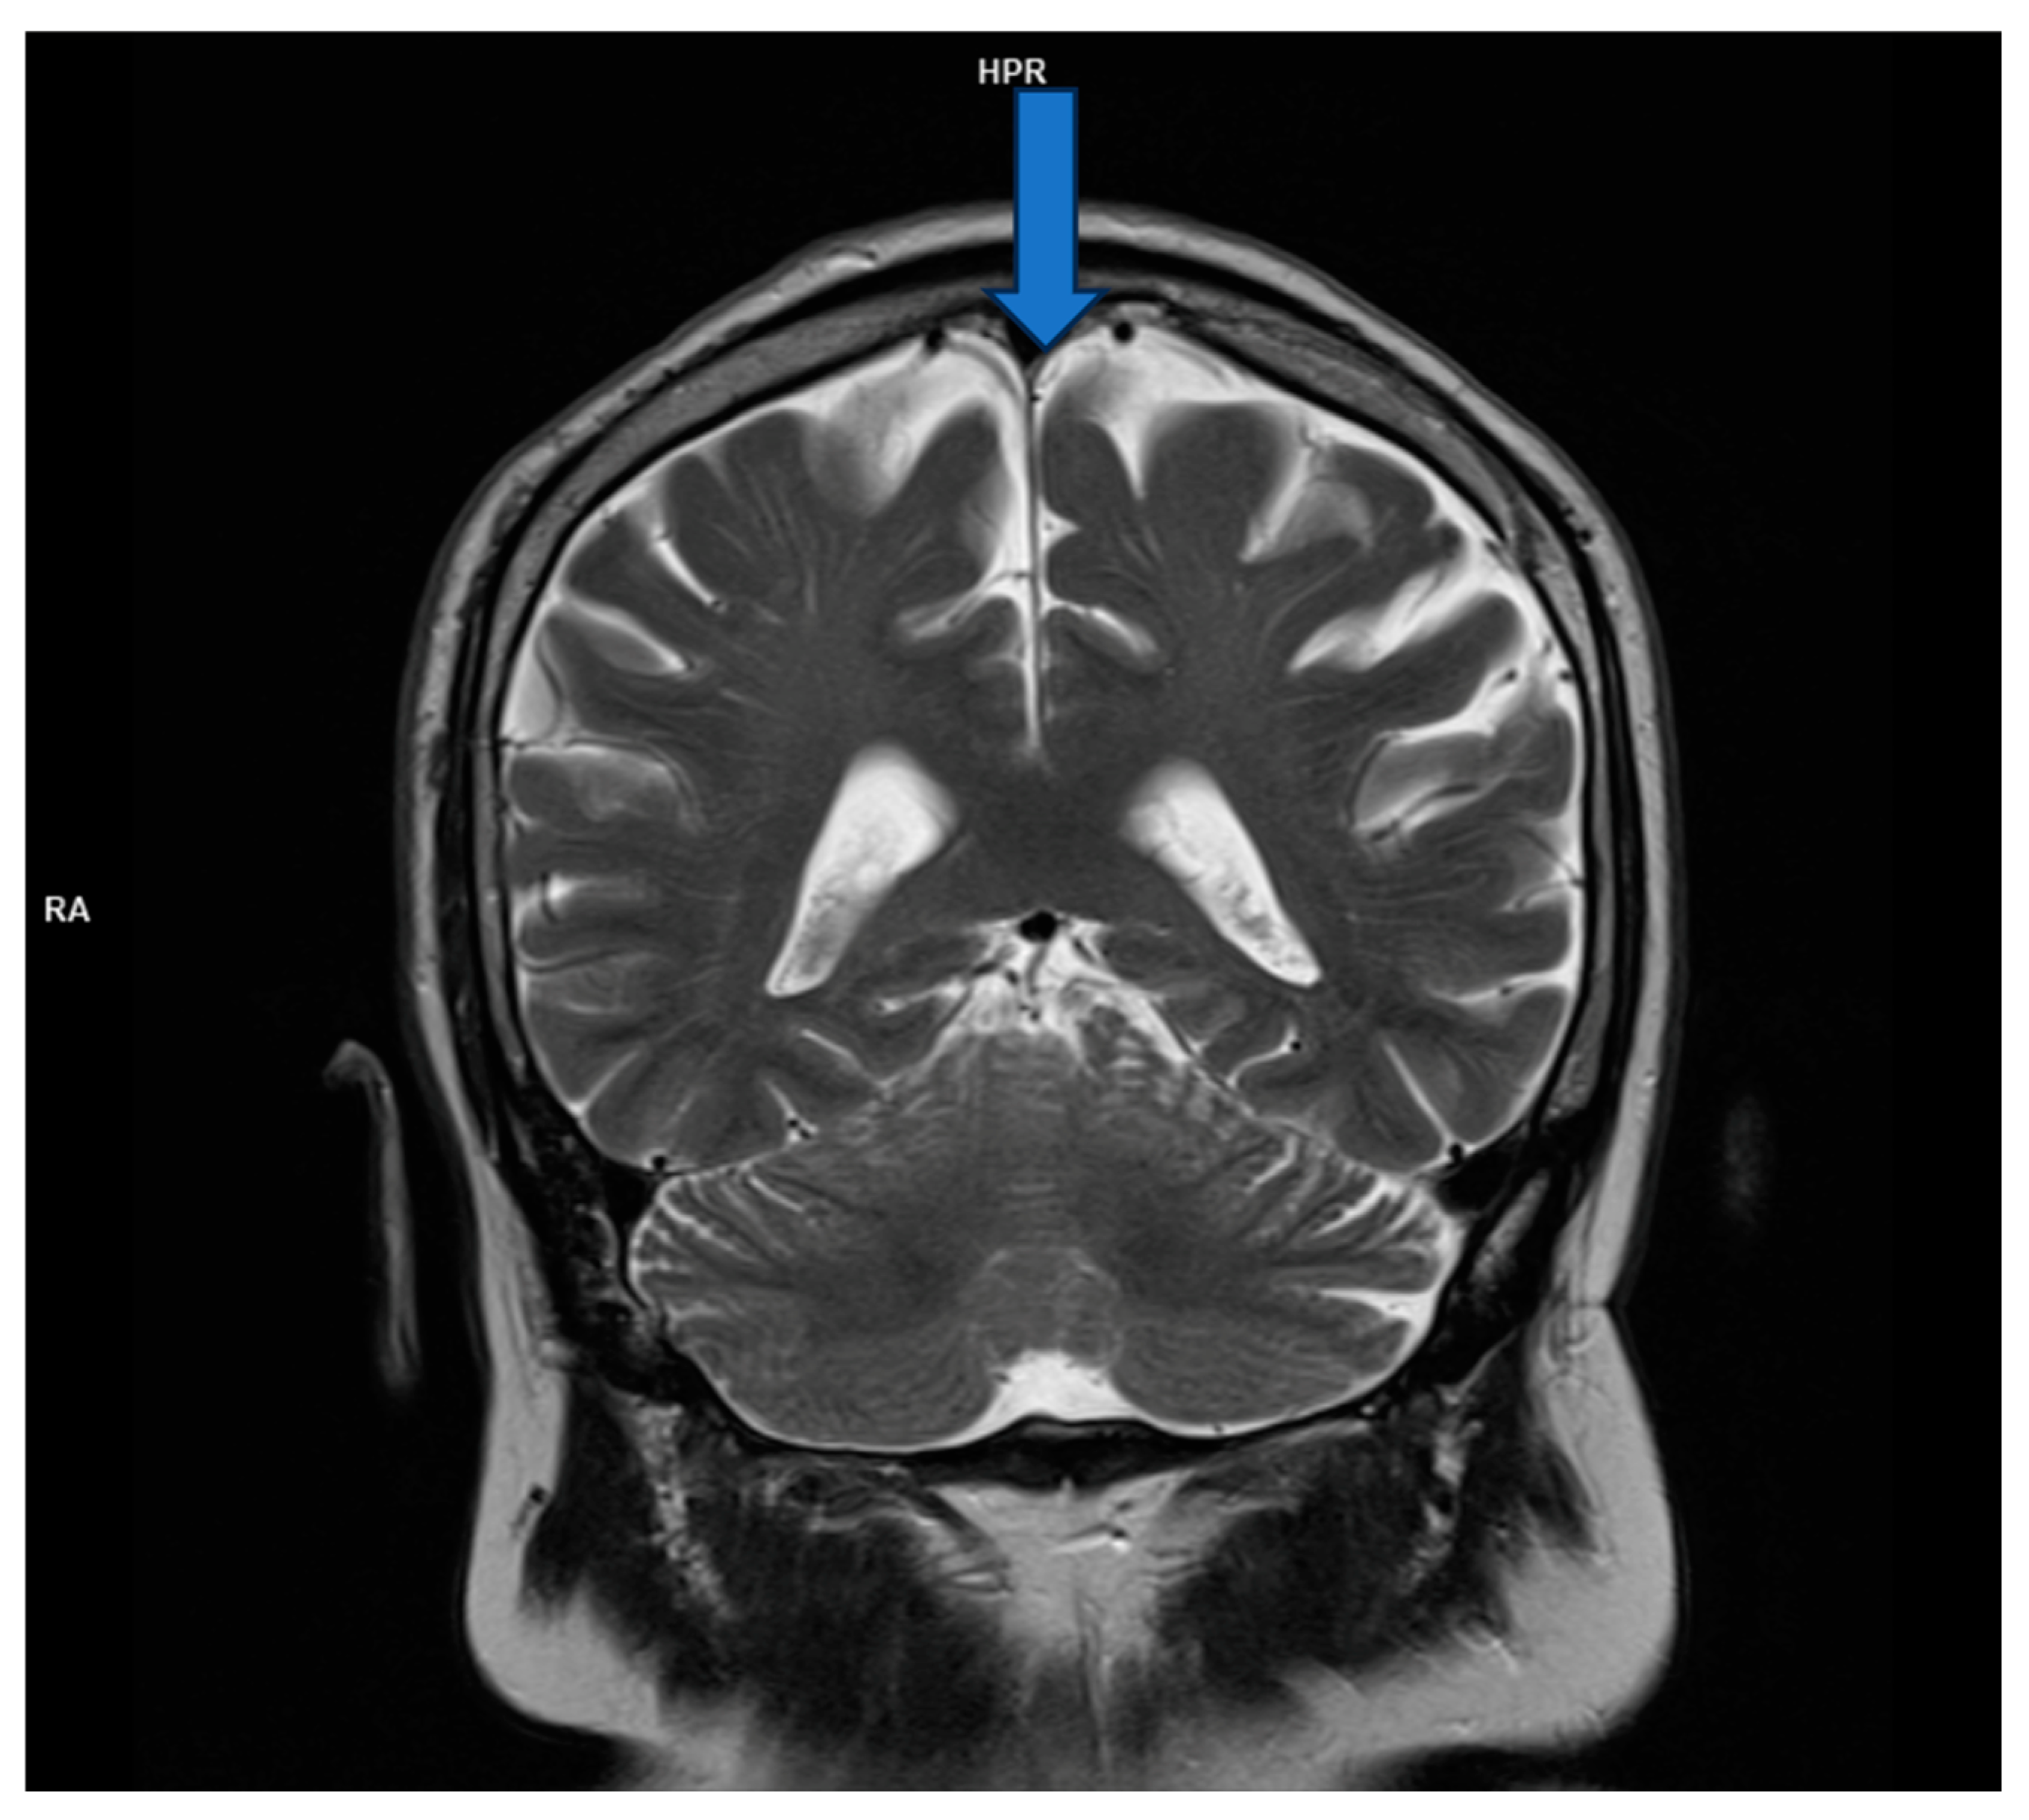

Magnetic resonance imaging (MRI) is a highly sensitive test (over 90%) for detecting herpes simplex encephalitis. Lesions appear hypodense on T1 and hyperintense on T2 and FLAIR, often affecting the temporal lobes, having progressed along the limbic system to the inferior frontal lobes and insular cortex. High-resolution FLAIR can reveal thalamic changes not visible on DWI, while the basal ganglia are usually unaffected. Immunocompromised patients may show atypical patterns outside the frontotemporal regions and often have widespread brain involvement, including the brainstem and cerebellum, but in one-third of patients, there are no pathological changes on MRI [8].

However, brain magnetic resonance imaging (MRI) revealed diffuse cortical atrophy with widened cerebrospinal fluid spaces and prominent perivascular spaces bilaterally in the subinsular region (Figure 1, Figure 2 and Figure 3).

Figure 1. MRI; T2 coronal section- cortical atrophic changes.